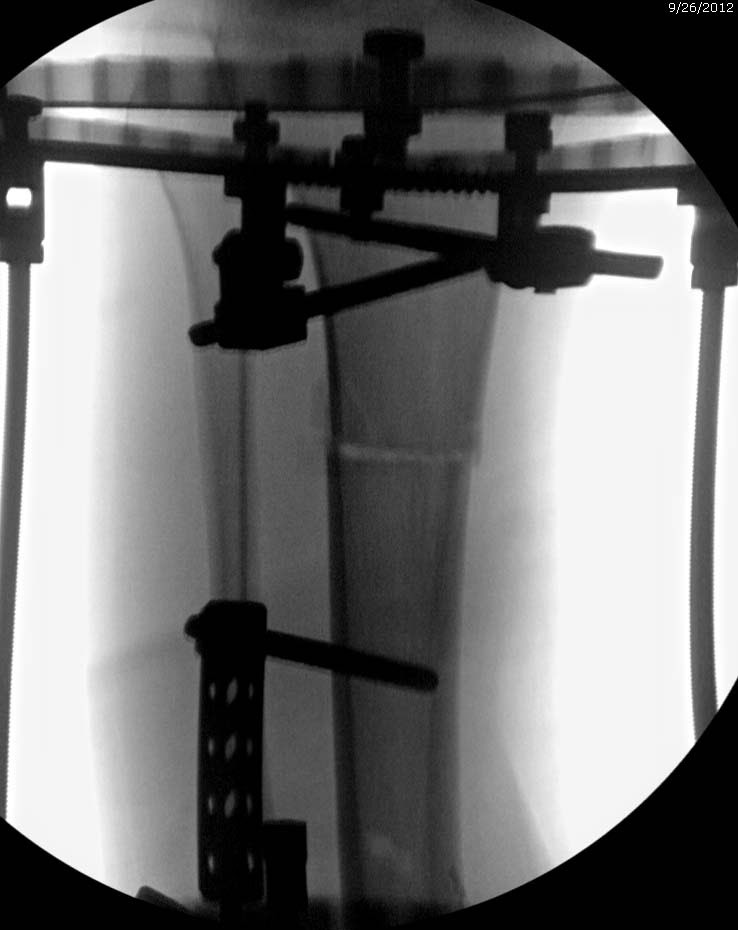

Данный случай не огнестрельная рана, а результат мотоциклетной аварии.

Независимо от повреждения при таких обширных дефектах мягких и костной

тканей применяется схожая тактика. Как видно, после нескольких I&D для

создания “pseudo membrane” применили цилиндрический блок из цемента.

Дефект мягких тканей закрыли свободным Anterior Thigh Graft. Из малого

доступа цилиндр удален небольшими кусочками, а пространство заполнили

бусами для освобождения пространства. По мере приближения регенерата

освободили пространство удалением бус через небольшой разрез. Этап

созревание регенерата можно было ускорить усилением интрамедуллярным

гвоздем, но решили закончить методом Илизарова.